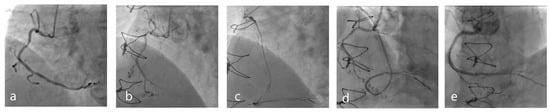

- De Winter, R.W.; Walsh, S.J.; Hanratty, C.G.; Spratt, J.C.; Sprengers, R.W.; Twisk, J.W.; Vegting, I.; Schumacher, S.P.; Bom, M.J.; Hoek, R.; et al. Percutaneous coronary intervention of native coronary artery versus saphenous vein graft in patients with prior coronary artery bypass graft surgery: Rationale and design of the multicenter, randomized PROCTOR trial. Am. Heart J. 2023, 257, 20–29. [Google Scholar] [CrossRef] [PubMed]